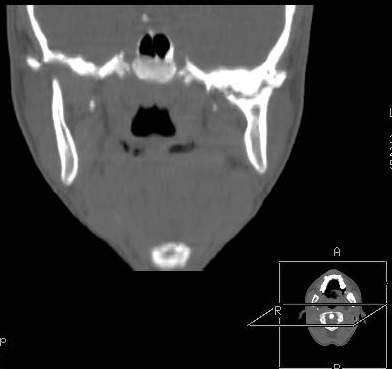

Пациент В., 13 лет. Диагноз: Костный анкилоз левого височно-нижнечелюстного сустава (ВНЧС), левосторонняя микрогения. Болеет с 2-х летнего возраста. Возможная причина развития анкилоза – воспалительный процесс (в первые 1,5 года жизни часто болел простудными заболеваниями, травму родители отрицают). В 3 и 5 лет проводилась редрессация – безуспешно.Прилагаются: ортопантомограмма, кадры СКТ с 3Д реконструкцией. Вопросы: определение тактики лечения – вид и сроки реконструктивно-пластической операции (этапов операции), а именно – неоартропластики и устранения микрогении, медикаментозная терапия в до- и послеоперационный период, ортодонтическое лечение.